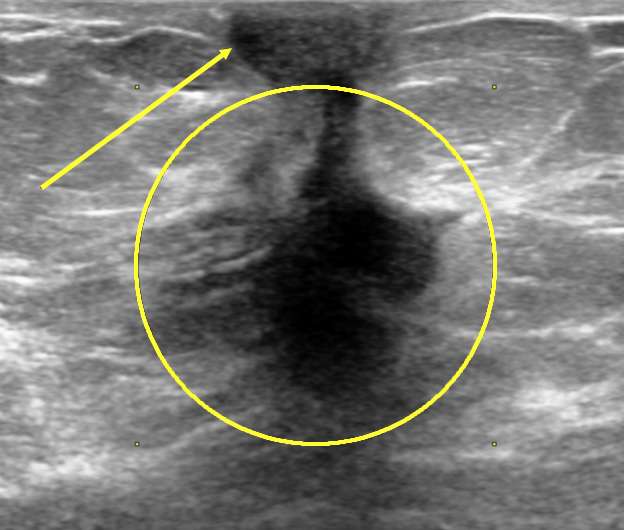

Figure 2: Skin Retraction on Ultrasound. Correlative grayscale ultrasound image demonstrates an irregular spiculated mass (circle). Skin retraction is difficult to appreciate on ultrasound (arrows), and is better evaluated on mammogram. Findings were consistent with biopsy proven invasive ductal carcinoma.